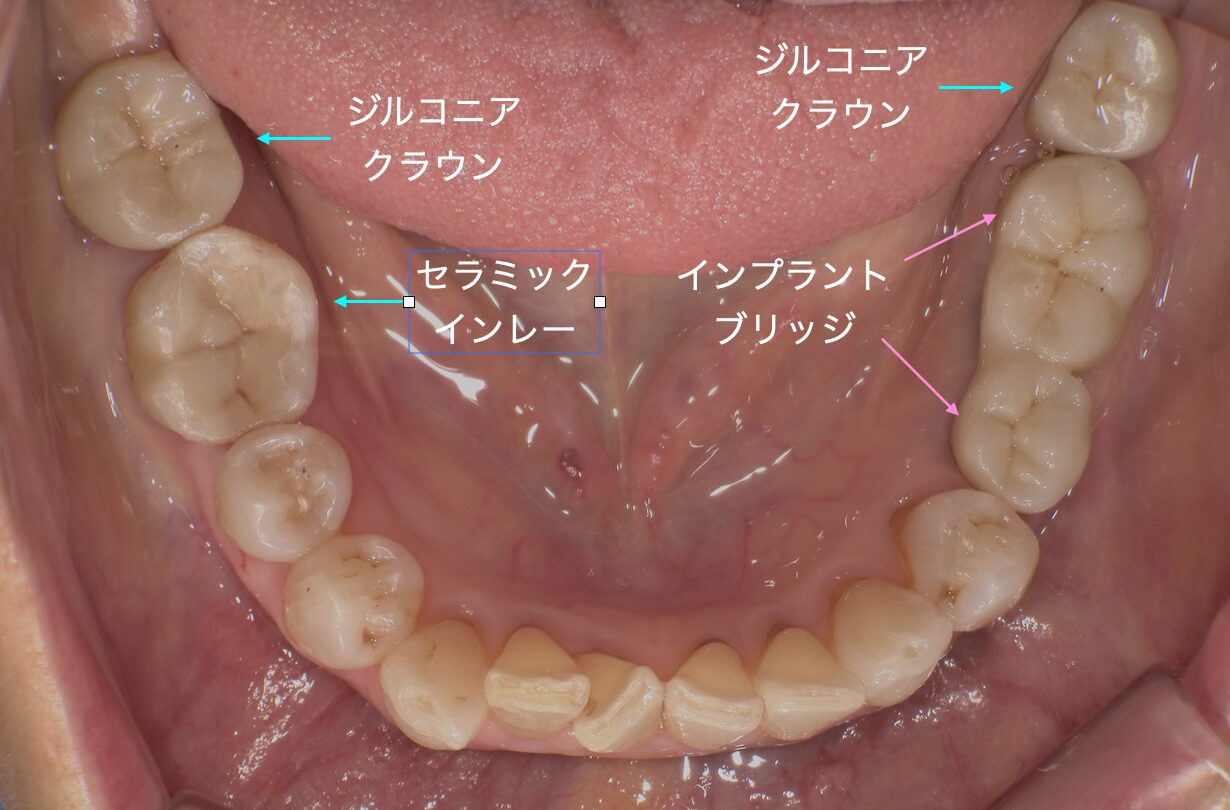

CASE 症例紹介

当院では、歯周病治療やインプラント治療、セラミック治療、審美治療など、様々な治療オプションを用いて、お口の中全体を管理しています。

院長が施術してきた症例をご確認のうえ、お気軽にご相談・ご来院ください。